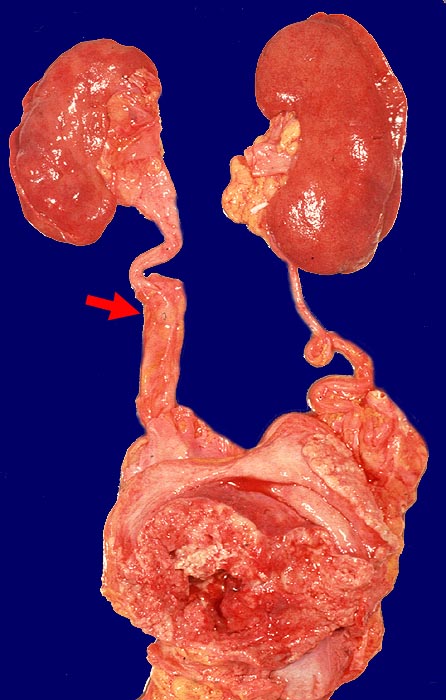

Urothelkarzinome entstehen zu über 90% in der Harnblase, können aber auch von Nierenbecken, Ureter oder Urethra ausgehen. Nicht selten sind multizentrische Tumoren (Feldeffekt der einwirkenden Noxen, Implantationsmetastasen). Bei Urothelkarzinomen der oberen Harnwege wird in einem Drittel bis zur Hälfte der Patienten später ein Blasenkarzinom gefunden.

Wenn keine Metastasen vorliegen, kann ein Patient durch radikale operative Eingriffe (Zystektomie mit pelviner Lymphknotendissektion, Nephrektomie) geheilt werden. Bei inoperablen Patienten sollten eine potentiell kurative Bestrahlung oder Chemo-/Radiotherapie erhalten. Bei den primär metastasierten Urothelkarzinomen versprechen Chemotherapien einen guten palliativen Effekt.

Makroskopie

Befund

Pathologischer Befund